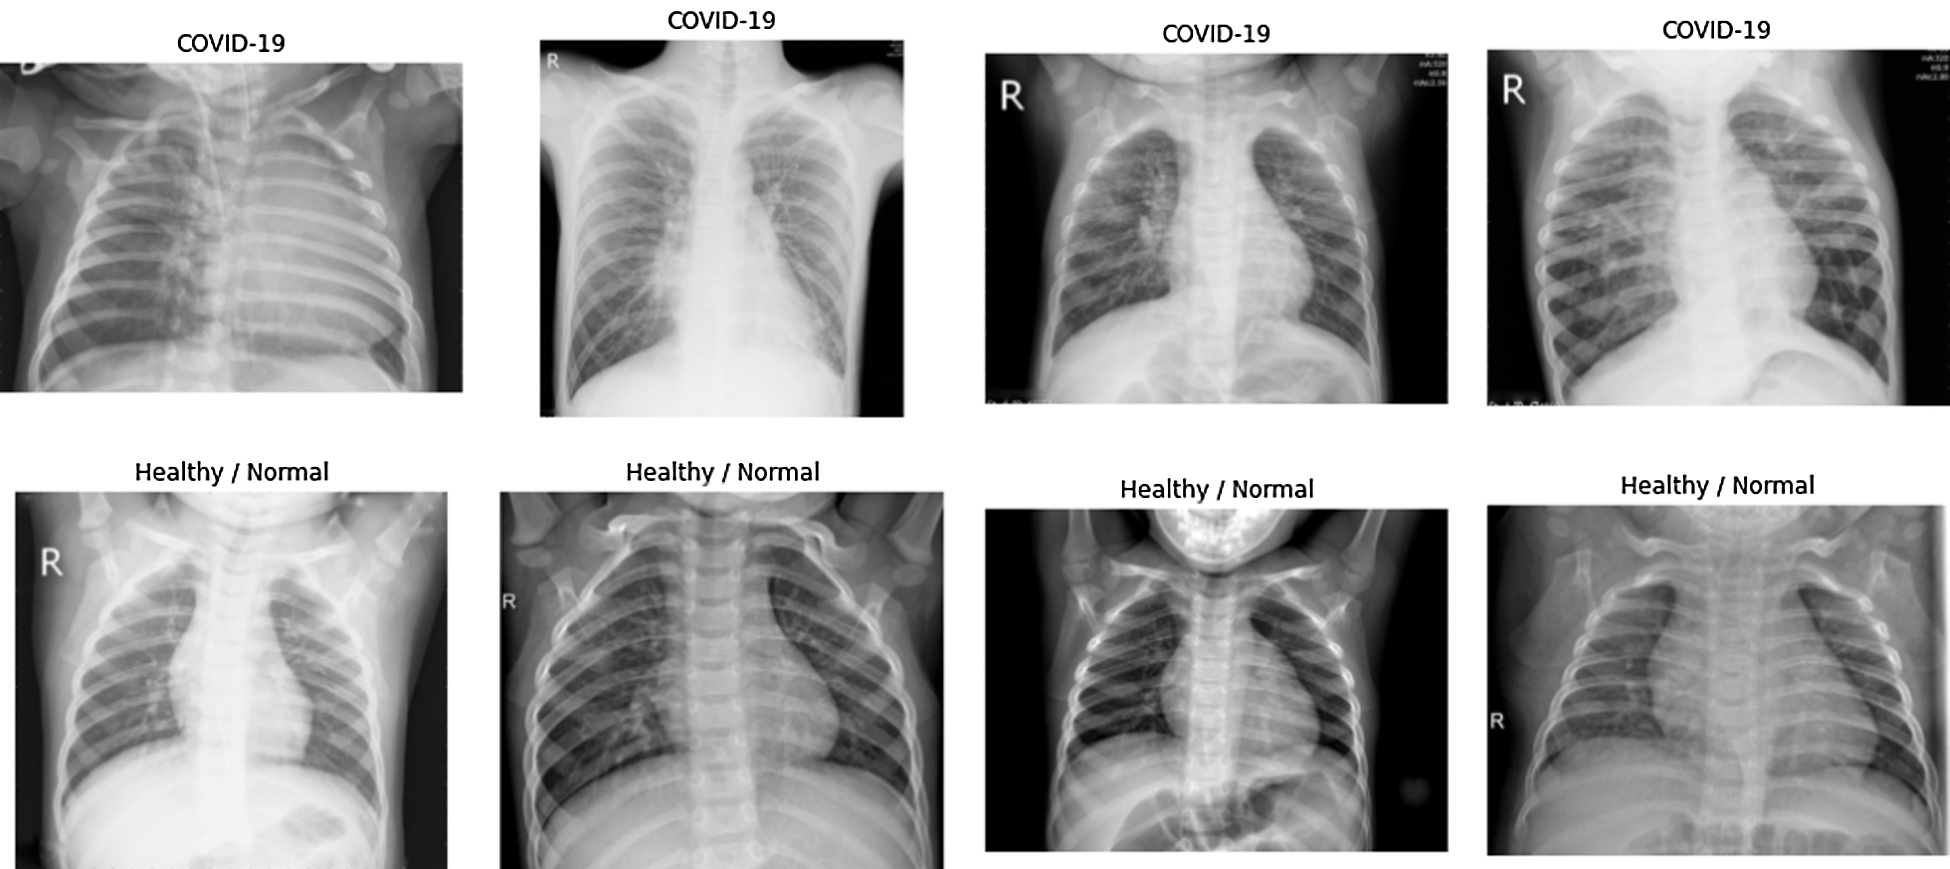

Fig. 4, shows the CT scans of COVID-19 infected patients and the healthy patients that are randomly selected from the dataset for visualization. Health professionals need to spend less time for identification by examining the varied representations. The convolutional neural network (CNN) is used to grab features and classify CT scans as COVID-19 affected and normal.

Figure 4: Dataset representation